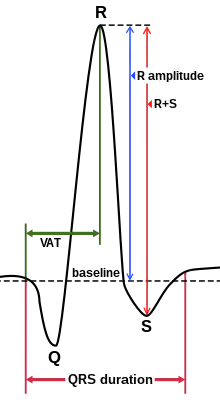

| Parameter | Normal value | Value comments | Clinical significance |

|---|---|---|---|

| QRS duration | 75 to 105 ms[3] | Shorter in children[4] | Prolonged duration could indicate hyperkalemia[5] or intraventricular conduction delay such as bundle branch block. |

| QRS amplitude |

|

Increased amplitude indicates cardiac hypertrophy | |

| Ventricular activation time (VAT) |

Measured in increased QRS amplitude[4] | ||

| Q wave | Abnormality indicates presence of infarction[6] | ||

| R wave | Large amplitude might indicate of left ventricular hypertrophy[8]

Duration longer than 45 ms might indicate left posterior fascicular block, LVH or LBBB.[9] | ||

| S wave | Large amplitude might indicate of left ventricular hypertrophy[10] |

Looking at the precordial leads, the R wave usually progresses from showing an rS-type complex in V1 with an increasing R and a decreasing S wave when moving toward the left side. There is usually a qR-type of complex in V5 and V6, with the R-wave amplitude usually taller in V5 than in V6. It is normal to have a narrow QS and rSr' patterns in V1, and this is also the case for qRs and R patterns in V5 and V6. The transition zone is where the QRS complex changes from predominantly negative to predominantly positive (R/S ratio becoming >1), and this usually occurs at V3 or V4. It is normal to have the transition zone at V2 (called "early transition") and at V5 (called "delayed transition").[11] In biomedical engineering, the maximum amplitude in the R wave is usually called "R peak amplitude", or just "R peak".[12][13] Accurate R peak detection is essential in signal processing equipment for heart rate measurement and it is the main feature used for arrhythmia detection.[14][15]

R wave peak time (RWPT) represents the time from the onset of QRS complex to the peak of R wave, which is usually measured in aVL and V5 or V6 leads.[16]

R-peak time for right ventricle is measured from leads V1 or V2, where upper range of normal is 35 ms. R wave peak time for left ventricle is measured from lead V5 or V6 and 45 ms is the upper range of normal.[7] R wave peak time is considered to be prolonged if it's more than 45 ms.